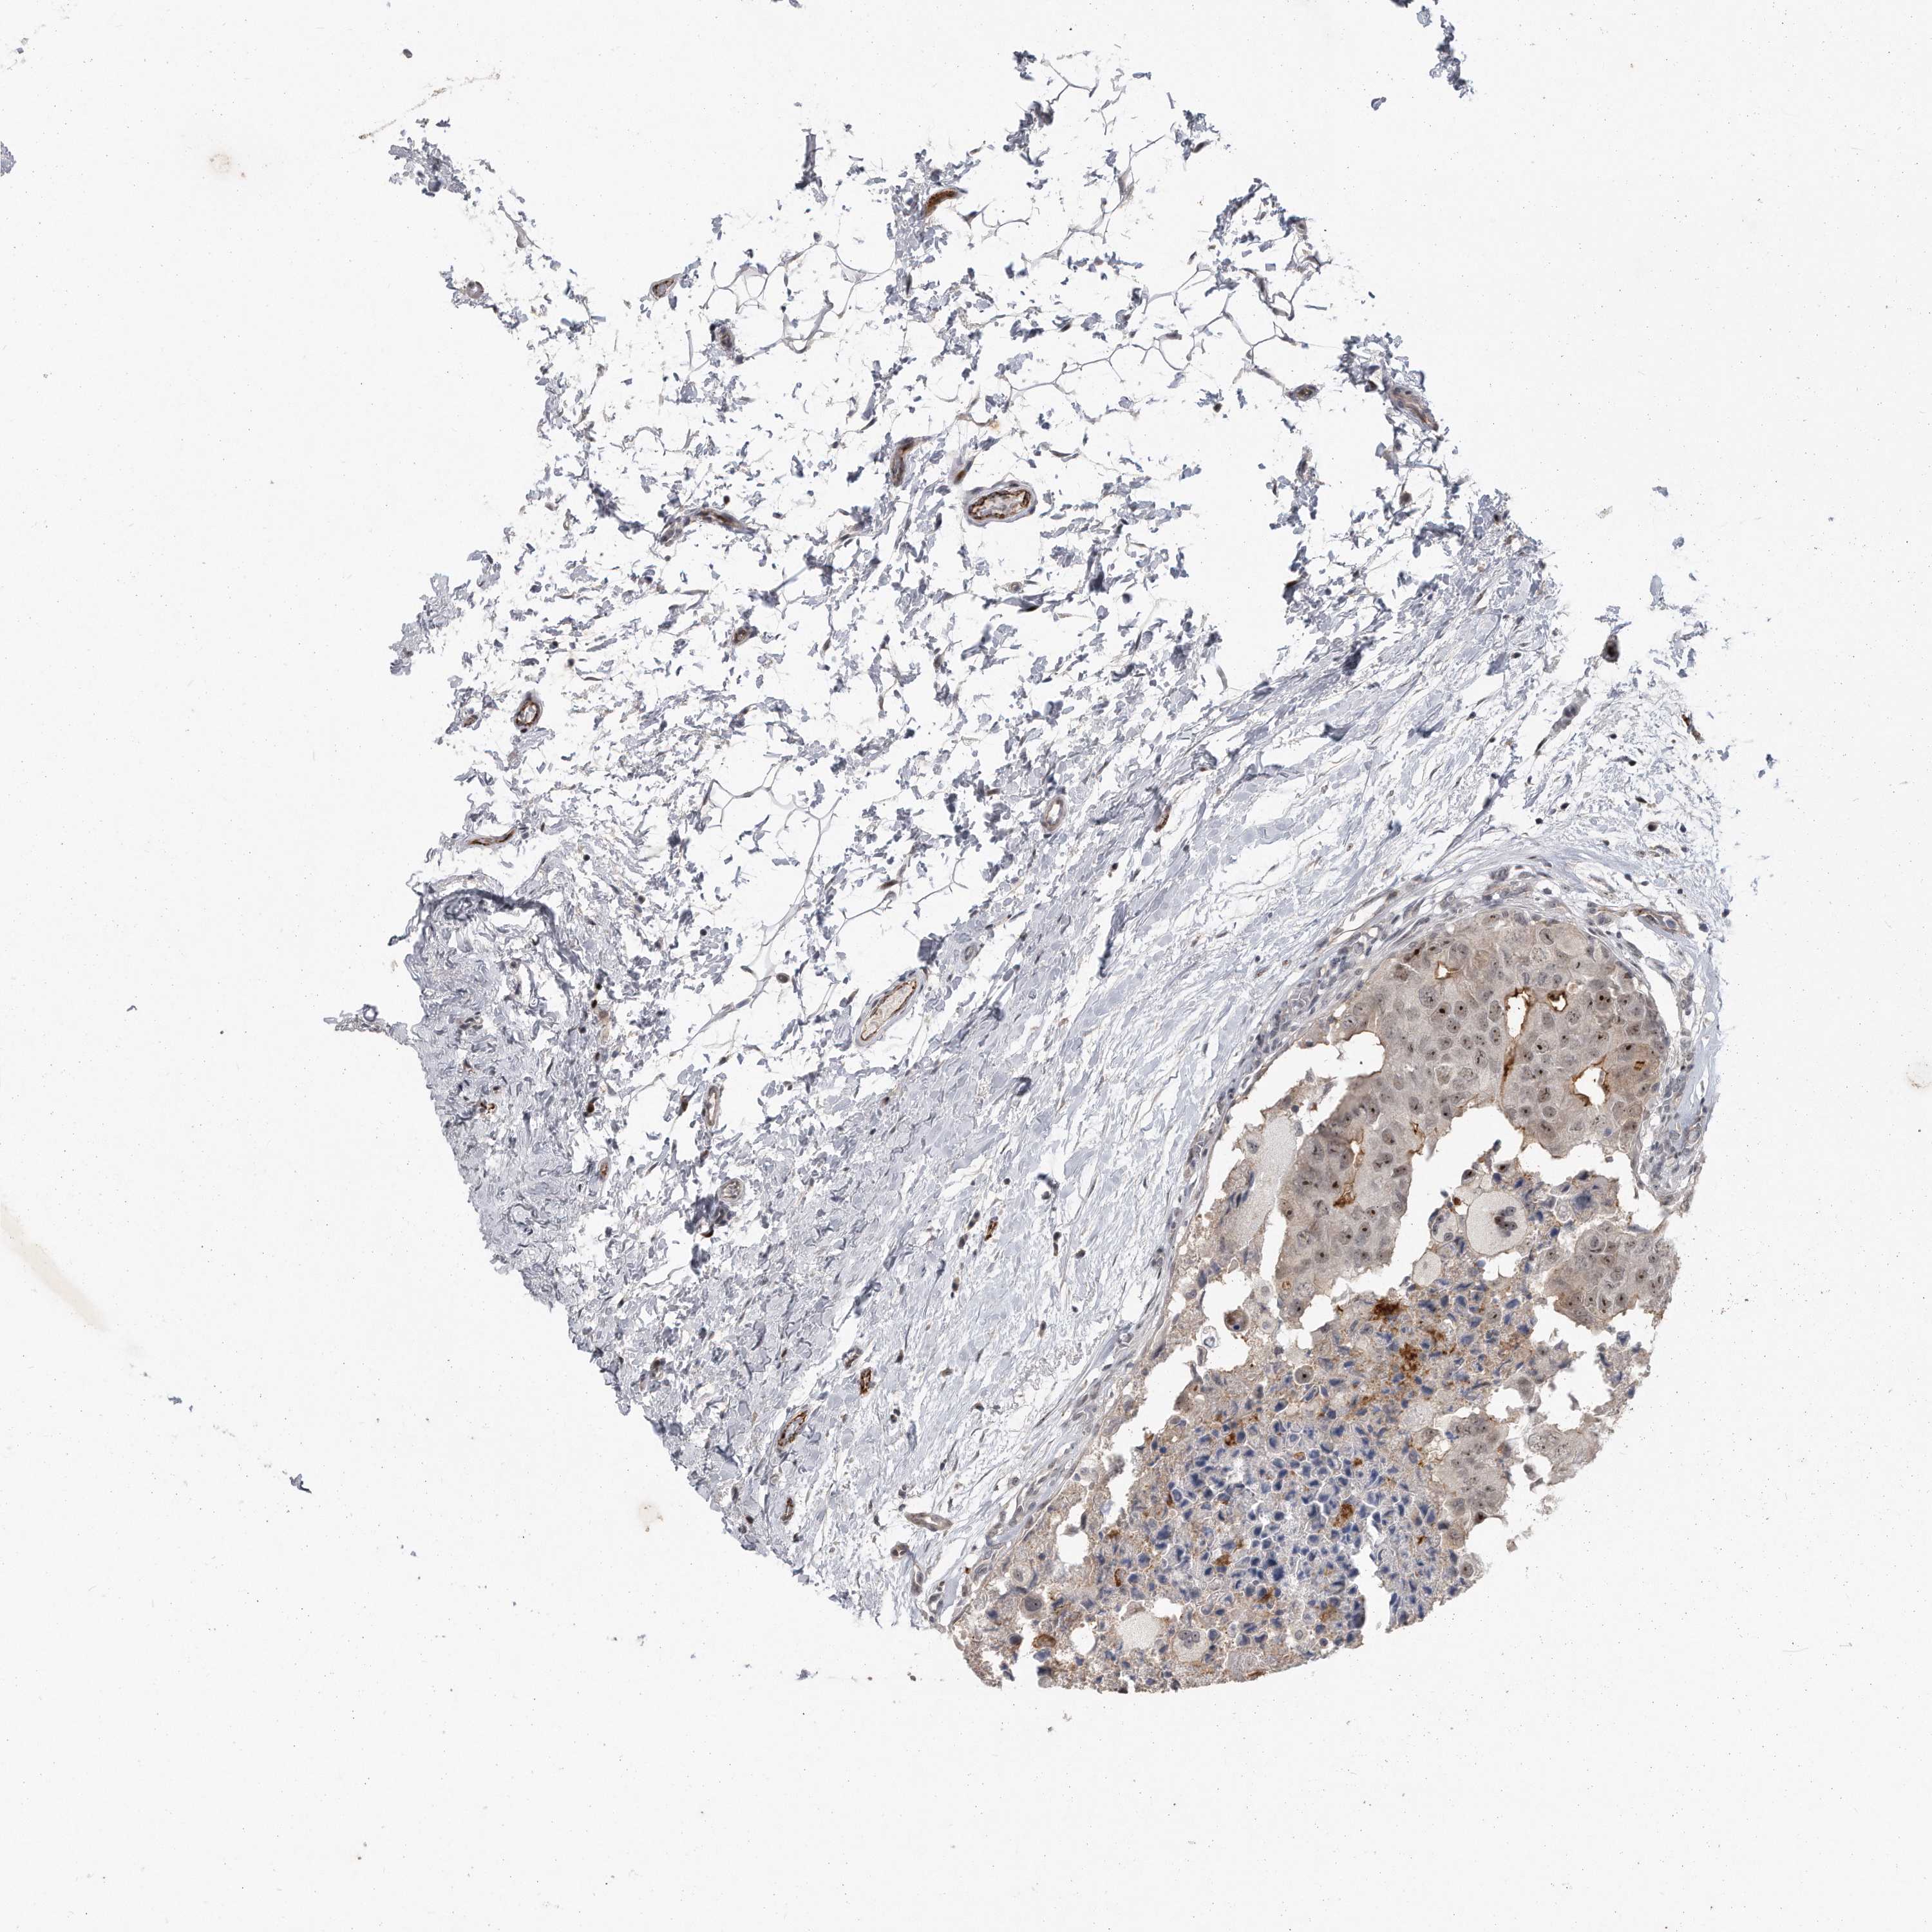

CANCER BREAST CANCER Show tissue menu

BRCA TCGA BRCA VALIDATION PROTEIN EXPRESSION

ANTIBODIES

AND

VALIDATION